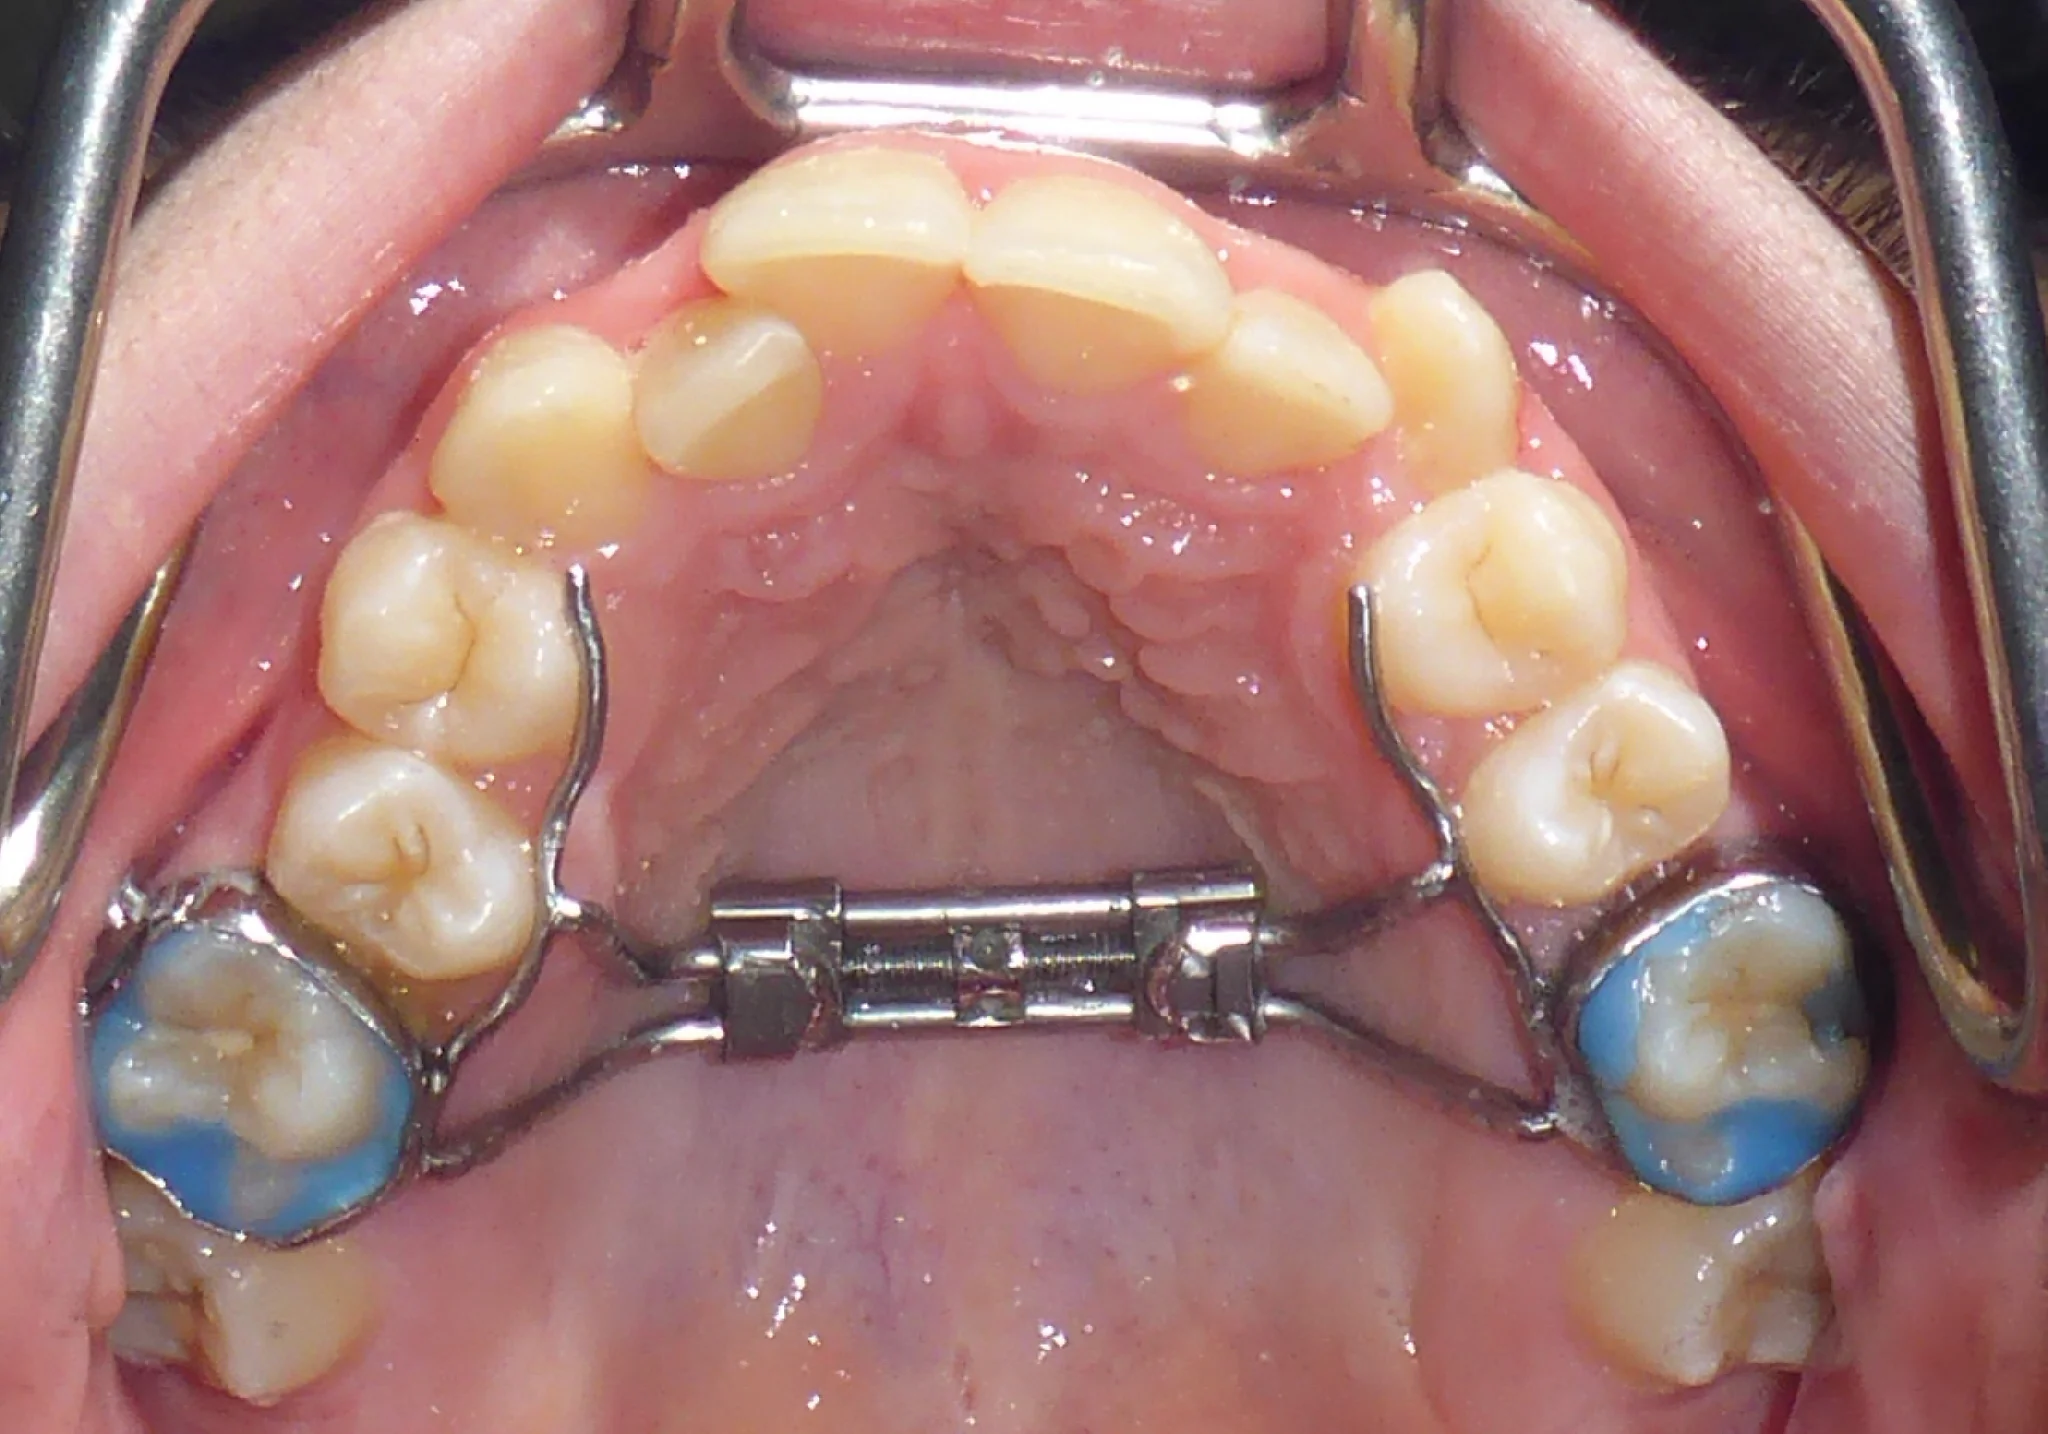

A palate expander (also called a rapid palatal expander or RPE) is an orthodontic device used to widen the upper jaw. It's attached to the upper molars and works by gently separating the bones of the palate.

2. Insert the key - Place the key in the hole in the center of the expander

3. Push toward the back - Gently push the key toward the back of the mouth until you see the next hole appear